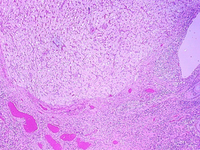

If a pregnancy does not occur, the uterine lining breaks down about 2 weeks after ovulation. Spiral arteries supplying the outer region of the uterine lining constrict and deprive the region of oxygenated blood. The cells lose fluid and cease to function. The stroma is invaded by leukocytes. Necrosis continues and the uterine lining is shed. This is the Menstral phase of the uterine lining. After the third or fourth day, all of the lining is shed except basal regions containing glands that can regenerate during the proliferative phase of the subsequent cycle. The following photograph illustrates the endometrium in the menstral phase. Note the few remaining glands. This region is called the BASALIS, whereas the region that is lost during menstruation is called the FUNCTIONALIS. The glands in the functionalis are the ones that become long during proliferative phase and tortuous during the secretory phase. Note the extravasated blood in the stroma of the endometrium.